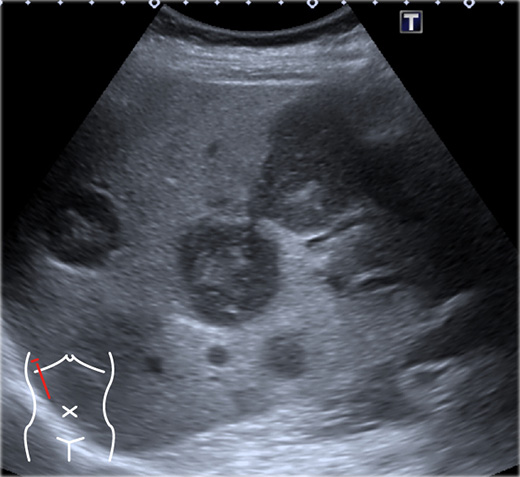

Imaging of the liver and pancreas – Vet Focus

Ultrasound of the liver, biliary tract, and pancreas | Abdominal Key

Ultrasound liver demonstrating a lesion inside the gallbladder …